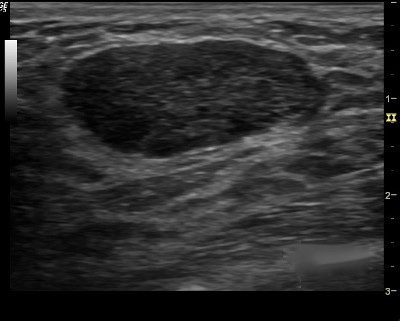

2. Finding none, you move on to the second step in the evaluation process and specifically look for one of the three strictly defined benign signs, and if any of them is found, the lesion can be considered BI-RADS 3.

3. The three benign findings defined by Stavros are:

- A purely hyperechoic lesion with no hypoechoic area larger than a normal duct or lobule.

- Elliptical, wider than tall, well-circumscribed and thin echogenic capsule.

- Gently lobulated, wider than tall, well-circumscribed and thin echogenic capsule.

– Combining the elliptical or gently lobulated shapes with the presence of a complete, thin echogenic capsule is necessary because many circumscribed carcinomas and most ductal carcinoma in situ are encompassed in a thin, echogenic capsule.